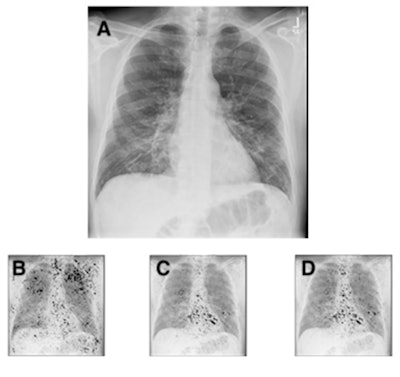

Chest radiograph (A) of a 63-year-old male patient with COVID-19 hospitalized for seven days, and with a body mass index of 26, demonstrating subtle ground-glass opacities in a lower lung distribution with increased geographic (0.34) and opacity scores (0.64). The integrated gradients saliency maps, with darker shades representing higher scores from the multitask comorbidity hierarchical condition category model: morbid obesity (B), congestive heart failure (C), cardiac arrhythmias (D). Much of the activation seen is outside the lung parenchyma, with notable activation of the axillary soft tissue for obesity (B) and heart for congestive heart failure and cardiac arrhythmias (C, D). The activations for congestive heart failure and cardiac arrhythmias are very similar, but they demonstrate subtle differences, with slightly greater activation at the left atrium and aortic knob (D), likely suggesting the associations of vascular disease and atrial fibrillation.Fifty-one (12.3%) of the patients had a full hospital admission, with all requiring supplemental oxygen. Four patients died. By combining data on comorbidities found on frontal chest x-rays, as well as adding patient age, the deep-learning model predicted prolonged hospitalization and supplemental oxygenation in ambulatory COVID-19 patients with an ROC AUC of 0.837 (95%, confidence interval: 0.791-0.883).